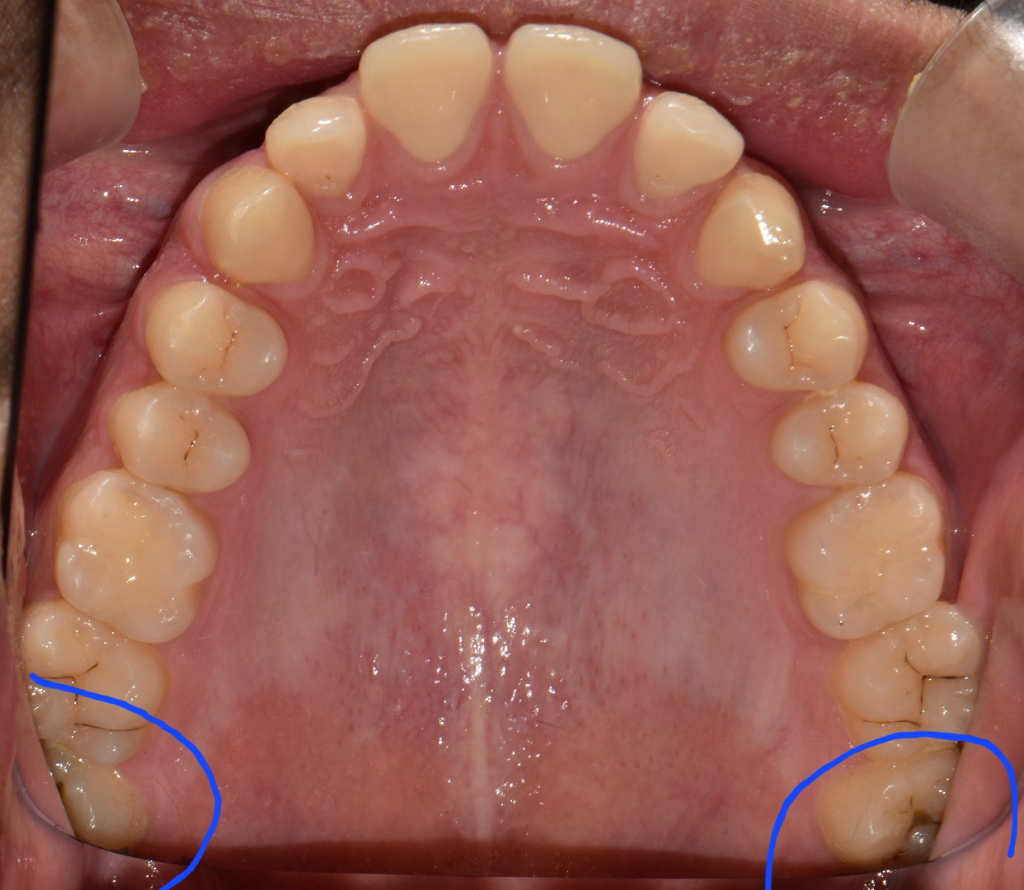

파랗게 그린쪽의 사랑니는 꼭 뽑으라고 원장님이 말씀하셔서 한달내로 예약잡고 발치하려는데, 저 사랑니는 다른케이스보다 뽑기 어려운가요? 완전매복이아니라 절개량이 적어 괜찮다는데 그럼 발치중,발치후 통증도 비교적 다른 케이스보단 덜할까요?

• 1번 째 사진